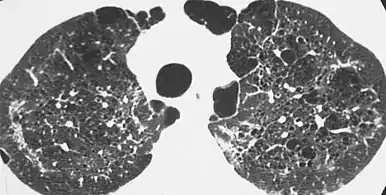

| CT scan of the lung showing bullae in the lower lung lobes of a subject with type alpha-1-antitrypsin deficiency. There is also increased lung density in areas with compression of lung tissue by the bullae. | |